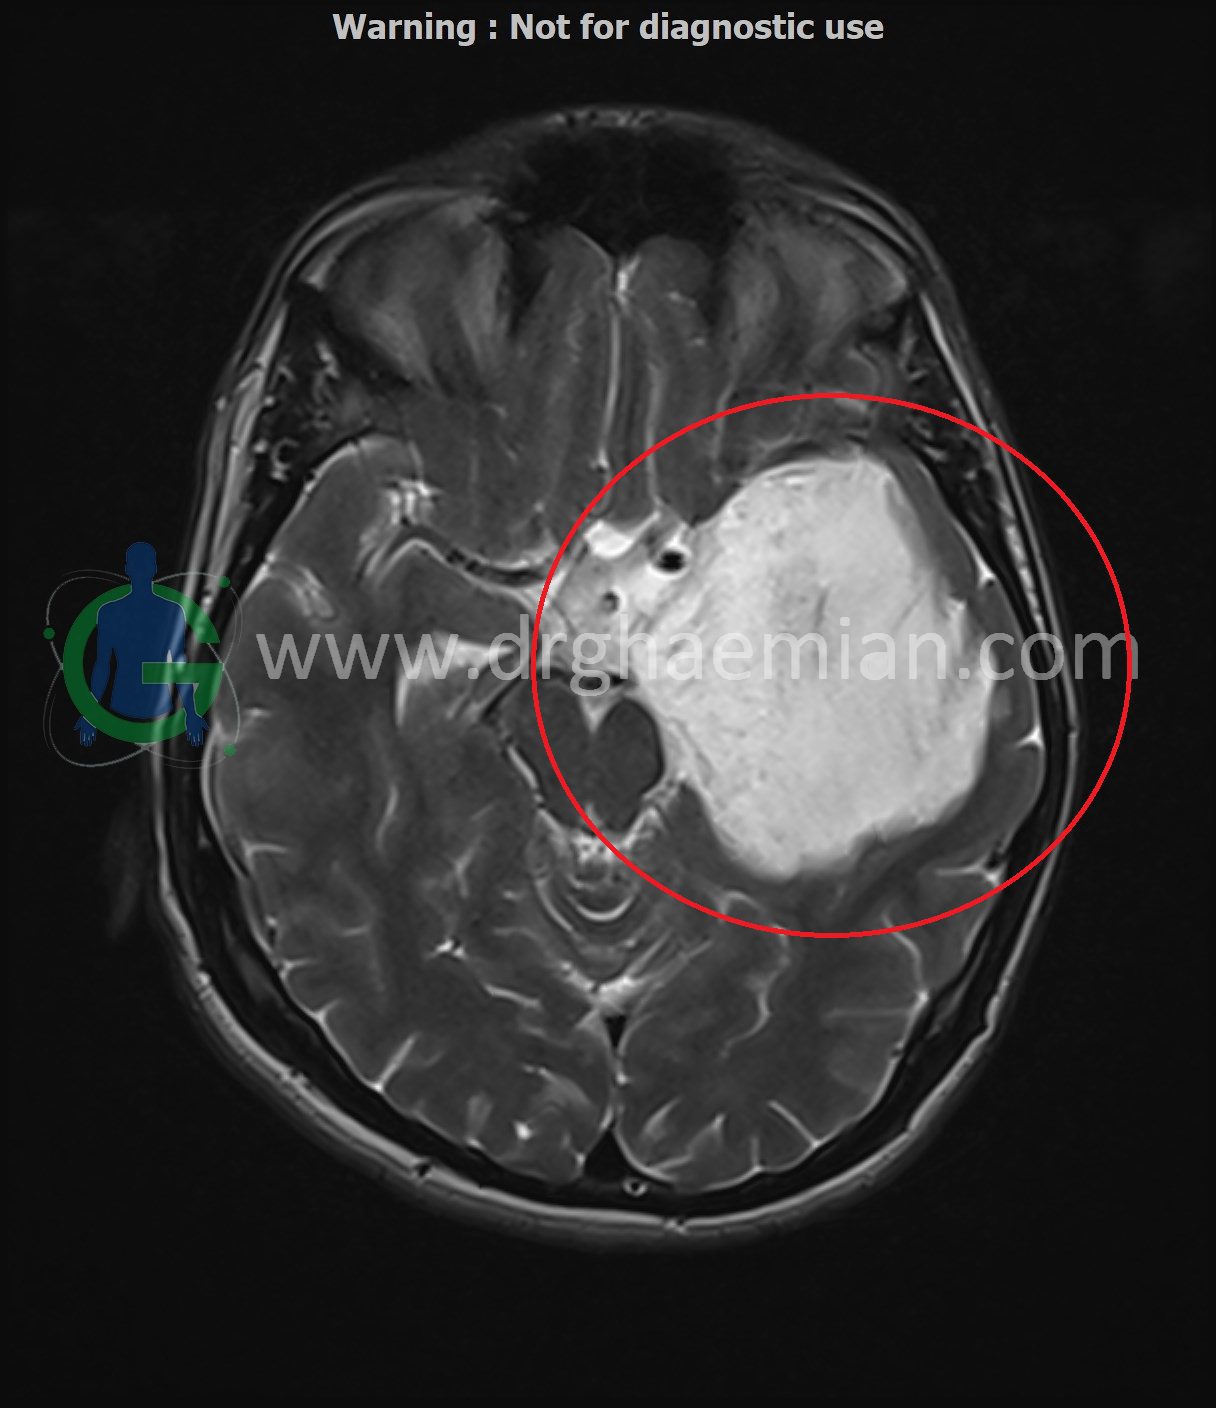

ام آر آی مغز یک روش تصویربرداری است که با استفاده از آهنربا های قوی و امواج رادیویی تصاویری از مغز و بافت های عصبی پیرامونی آن  ایجاد می کند.در این کیس کیست اپیدرموئید سر با احتمال وجود کیست اراکنوئید و…. دیده میشود

Extra-axial lesion: A large extra-axial cystic lesion, measuring approximately 81 x 51 x 61 mm, is located in the left middle fossa. This lesion exerts compression on the adjacent temporal and frontal lobes, as well as on the left basal ganglia and left midbrain. A midline shift of approximately 6.5 mm to the right side is noted.

Signal characteristics: The lesion shows T1 hypointensity and T2 hyperintensity with mild heterogeneous and “dirty” signal intensity when compared to cerebrospinal fluid (CSF). The heterogeneous signal characteristics raise concern for an epidermoid cyst, which is at the top of the differential diagnosis, with an arachnoid cyst being less likely.

Suspicious extension: Suspicious medial extension of the lesion into the suprasellar cistern is noted.

Recommendation: Due to the heterogeneous signal intensity, correlation with DWI sequences is highly recommended for further evaluation. Although the lesion’s location is typical for an arachnoid cyst, the signal intensity is more in favor of an epidermoid cyst.

Large extra-axial cystic lesion in the left middle fossa, with compression effects on adjacent brain structures and a 6.5 mm midline shift to the right.

The signal characteristics and location suggest an epidermoid cyst as the primary diagnosis, with an arachnoid cyst being less likely.

Further evaluation with DWI sequences is recommended.